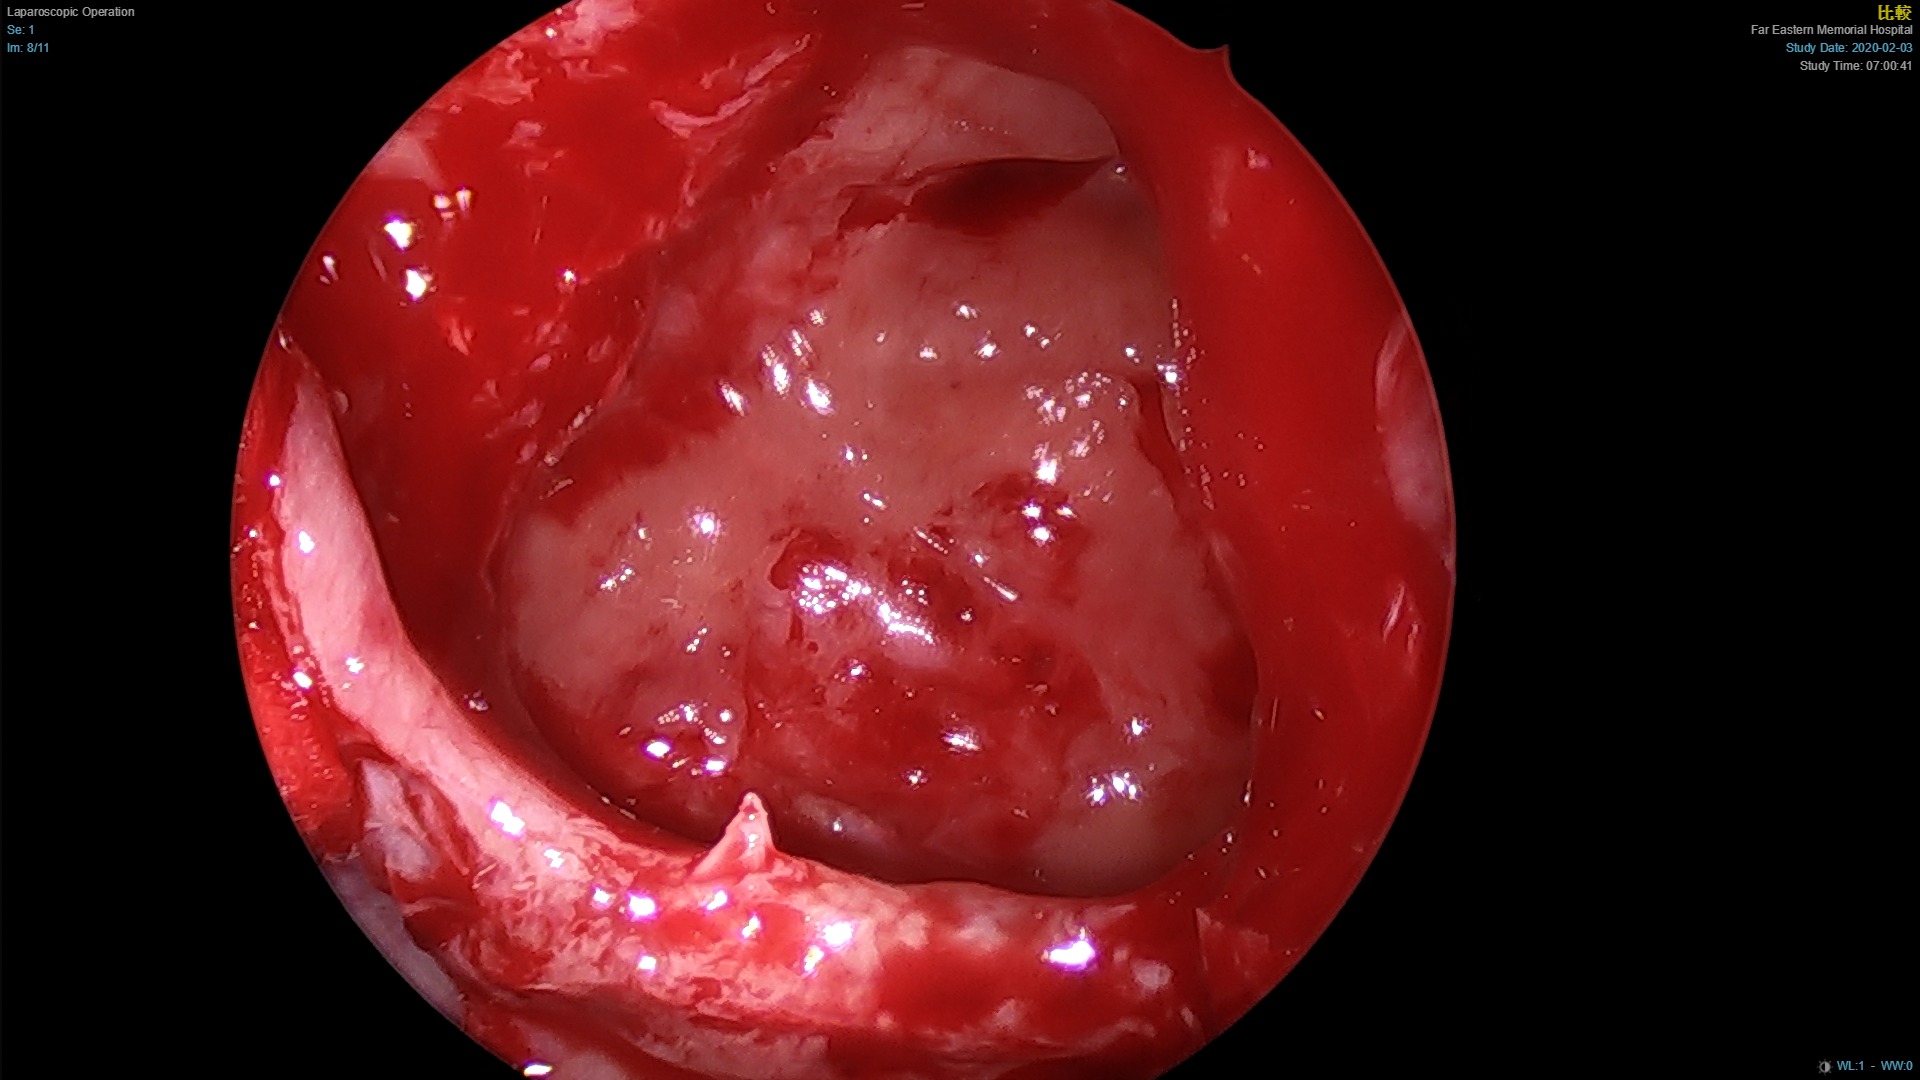

左側鼻竇炎之內視鏡手術,將鼻竇開口擴張,清除鼻竇內膿液